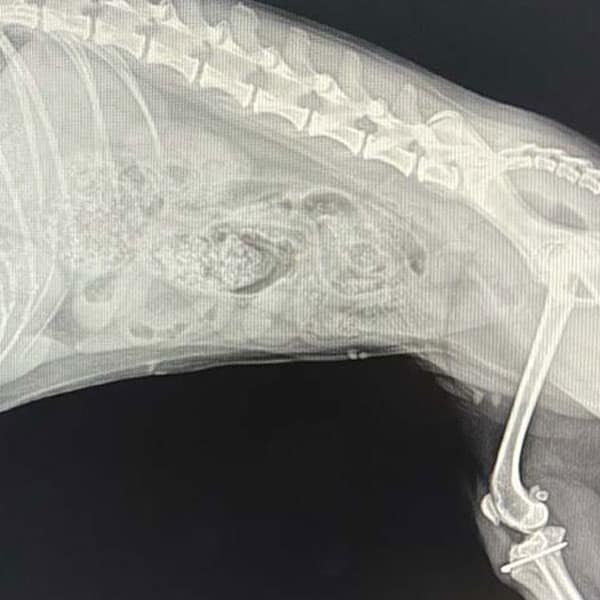

X-Ray & Diagnostic Imaging in Dacula

HPAH offers a state of the art digital X-ray machine which allows virtually no room for error and beautiful pictures that can be saved on a disc or emailed to a specialist if the need arises.